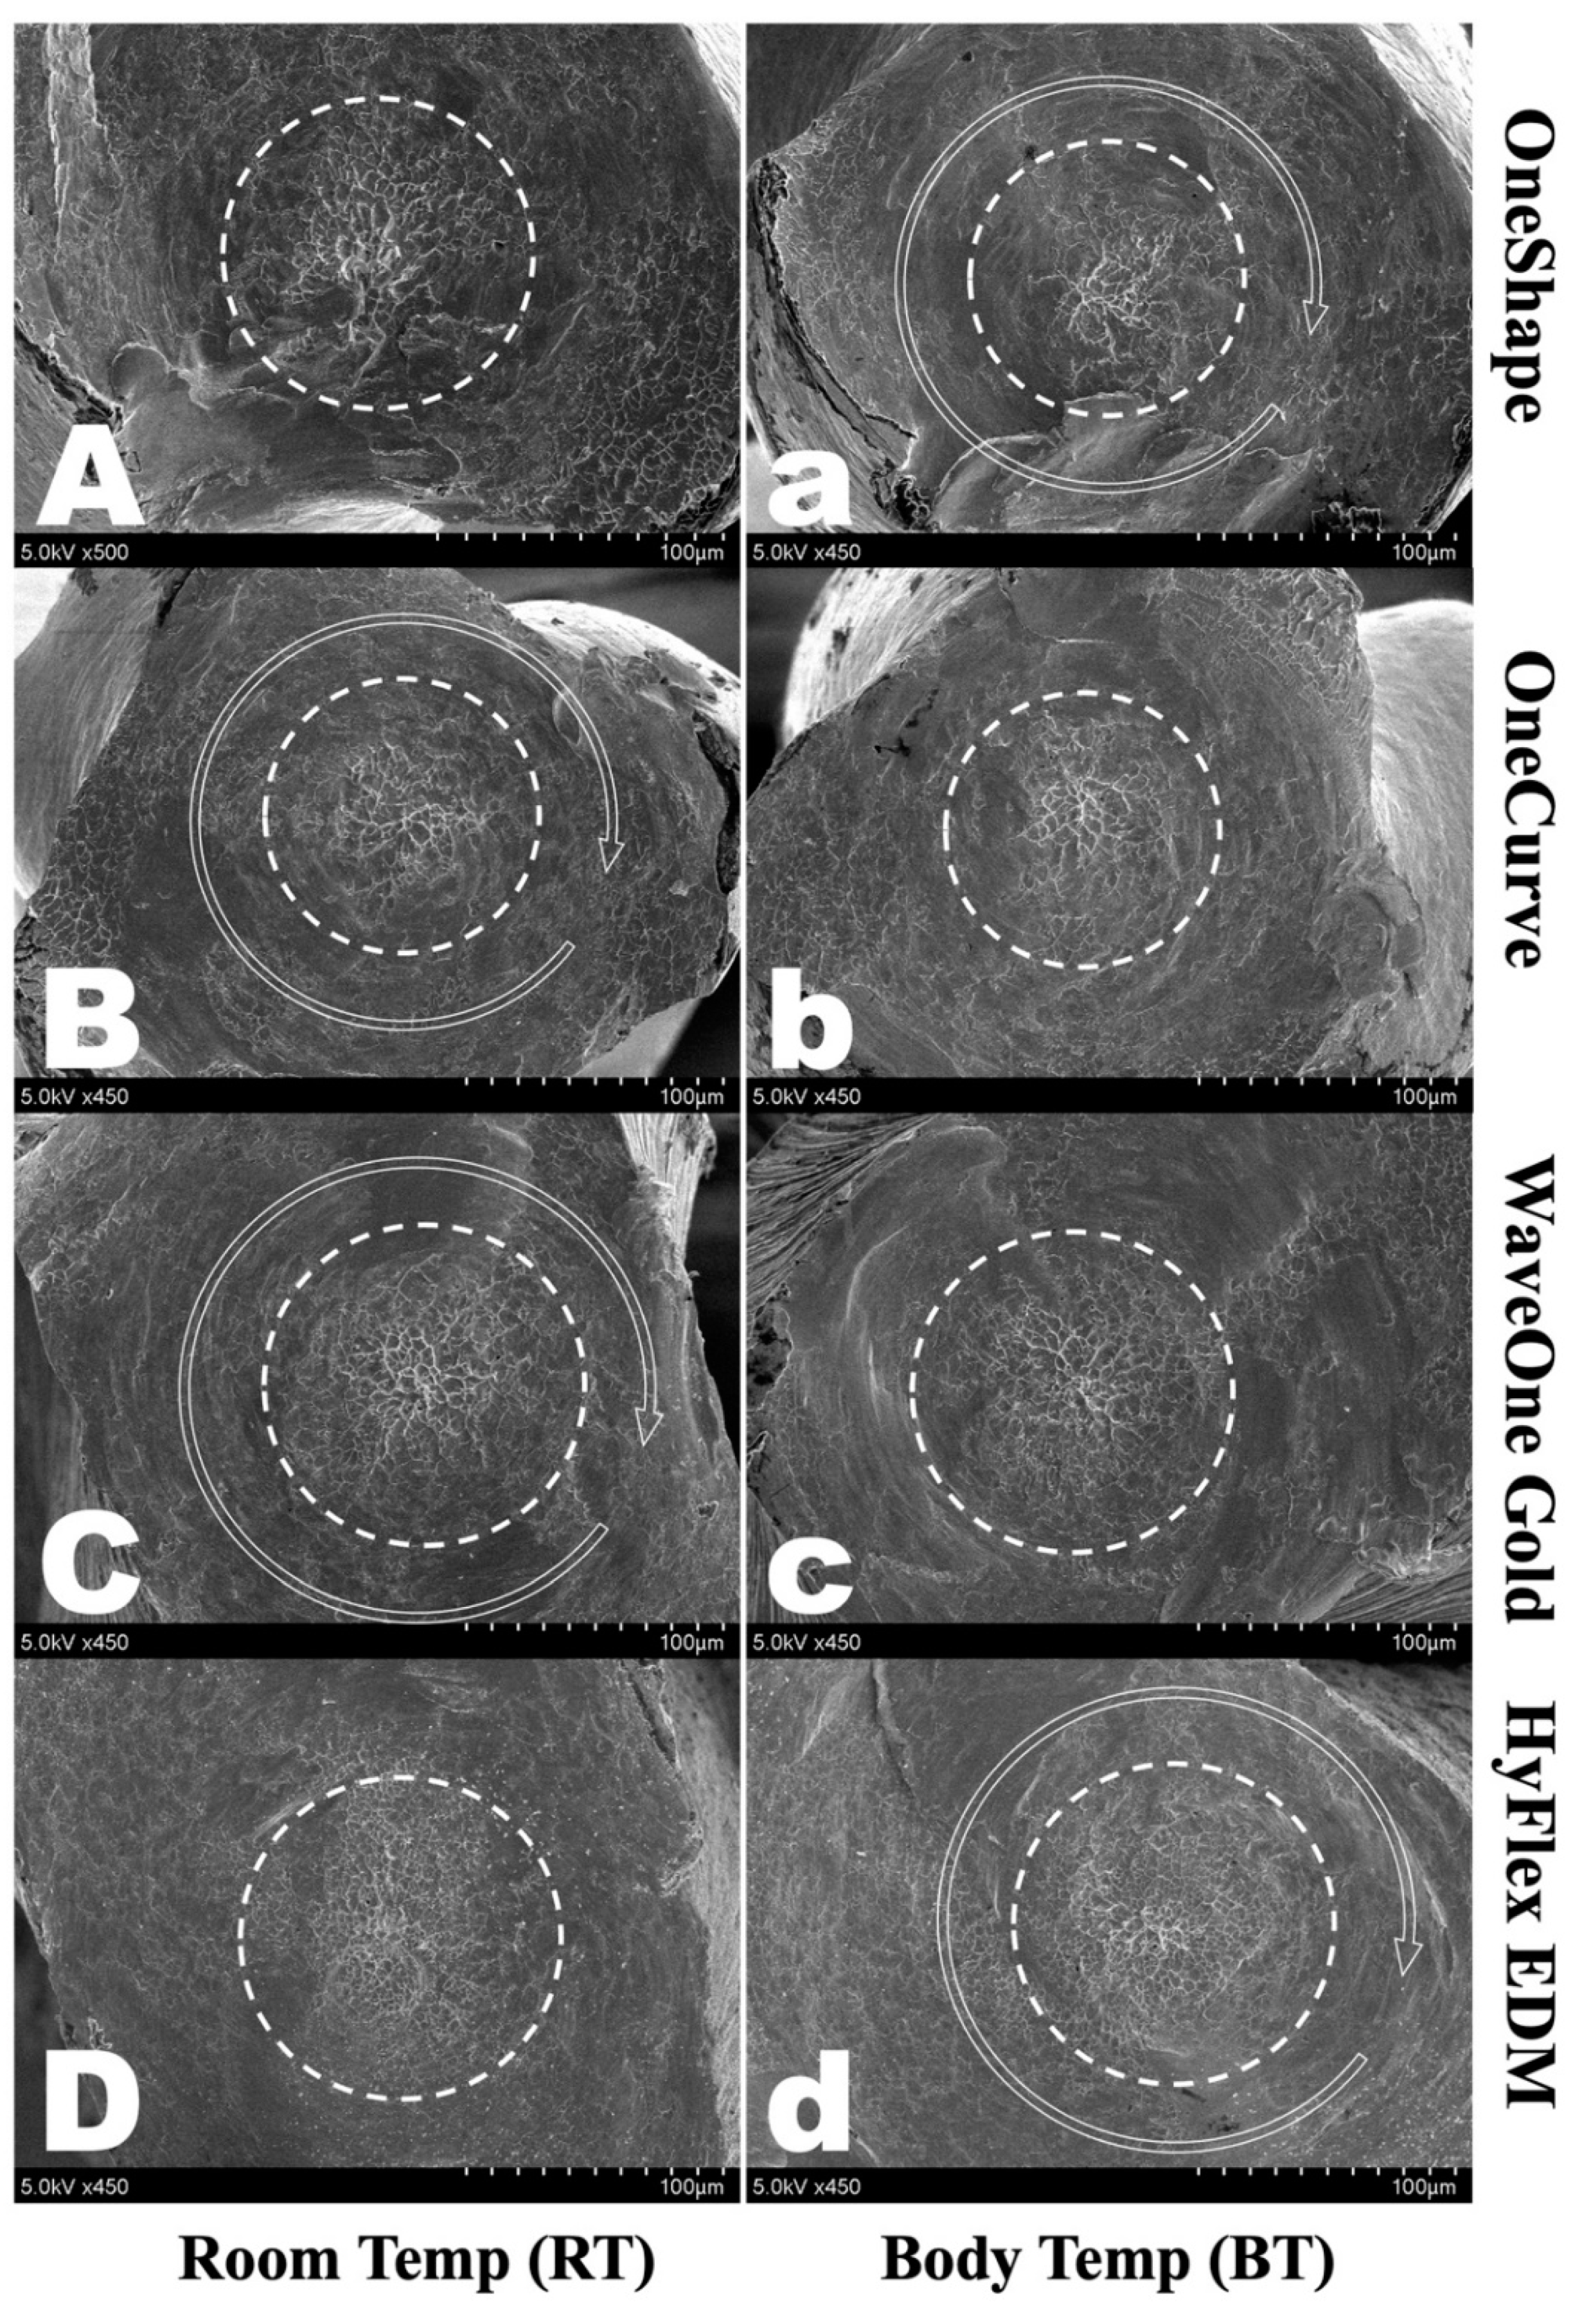

3.3. Scanning Electronic Microscopic Analysis

SEM examination of the fractured cross-sectional surfaces revealed typical features of torsional fractures, concentric abrasion marks and fibrous dimples from the torsional center (Figure 3). Furthermore, no topographical difference was observed between instruments in different temperature groups.

Figure 3.

Scanning electron micrographs of the fracture surface of fractured segments after the torsional test. All showed typical features of torsional fractures, including concentric abrasion marks (round arrow) and fibrous dimples (dotted circle). OneShape (OS) (A) RT and (a) BT, OneCurve (OC) (B) RT and (b) BT, WaveOne Gold (WOG) (C) RT and (c) BT, HyFlex EDM (HFE) (D) RT and (d) BT.